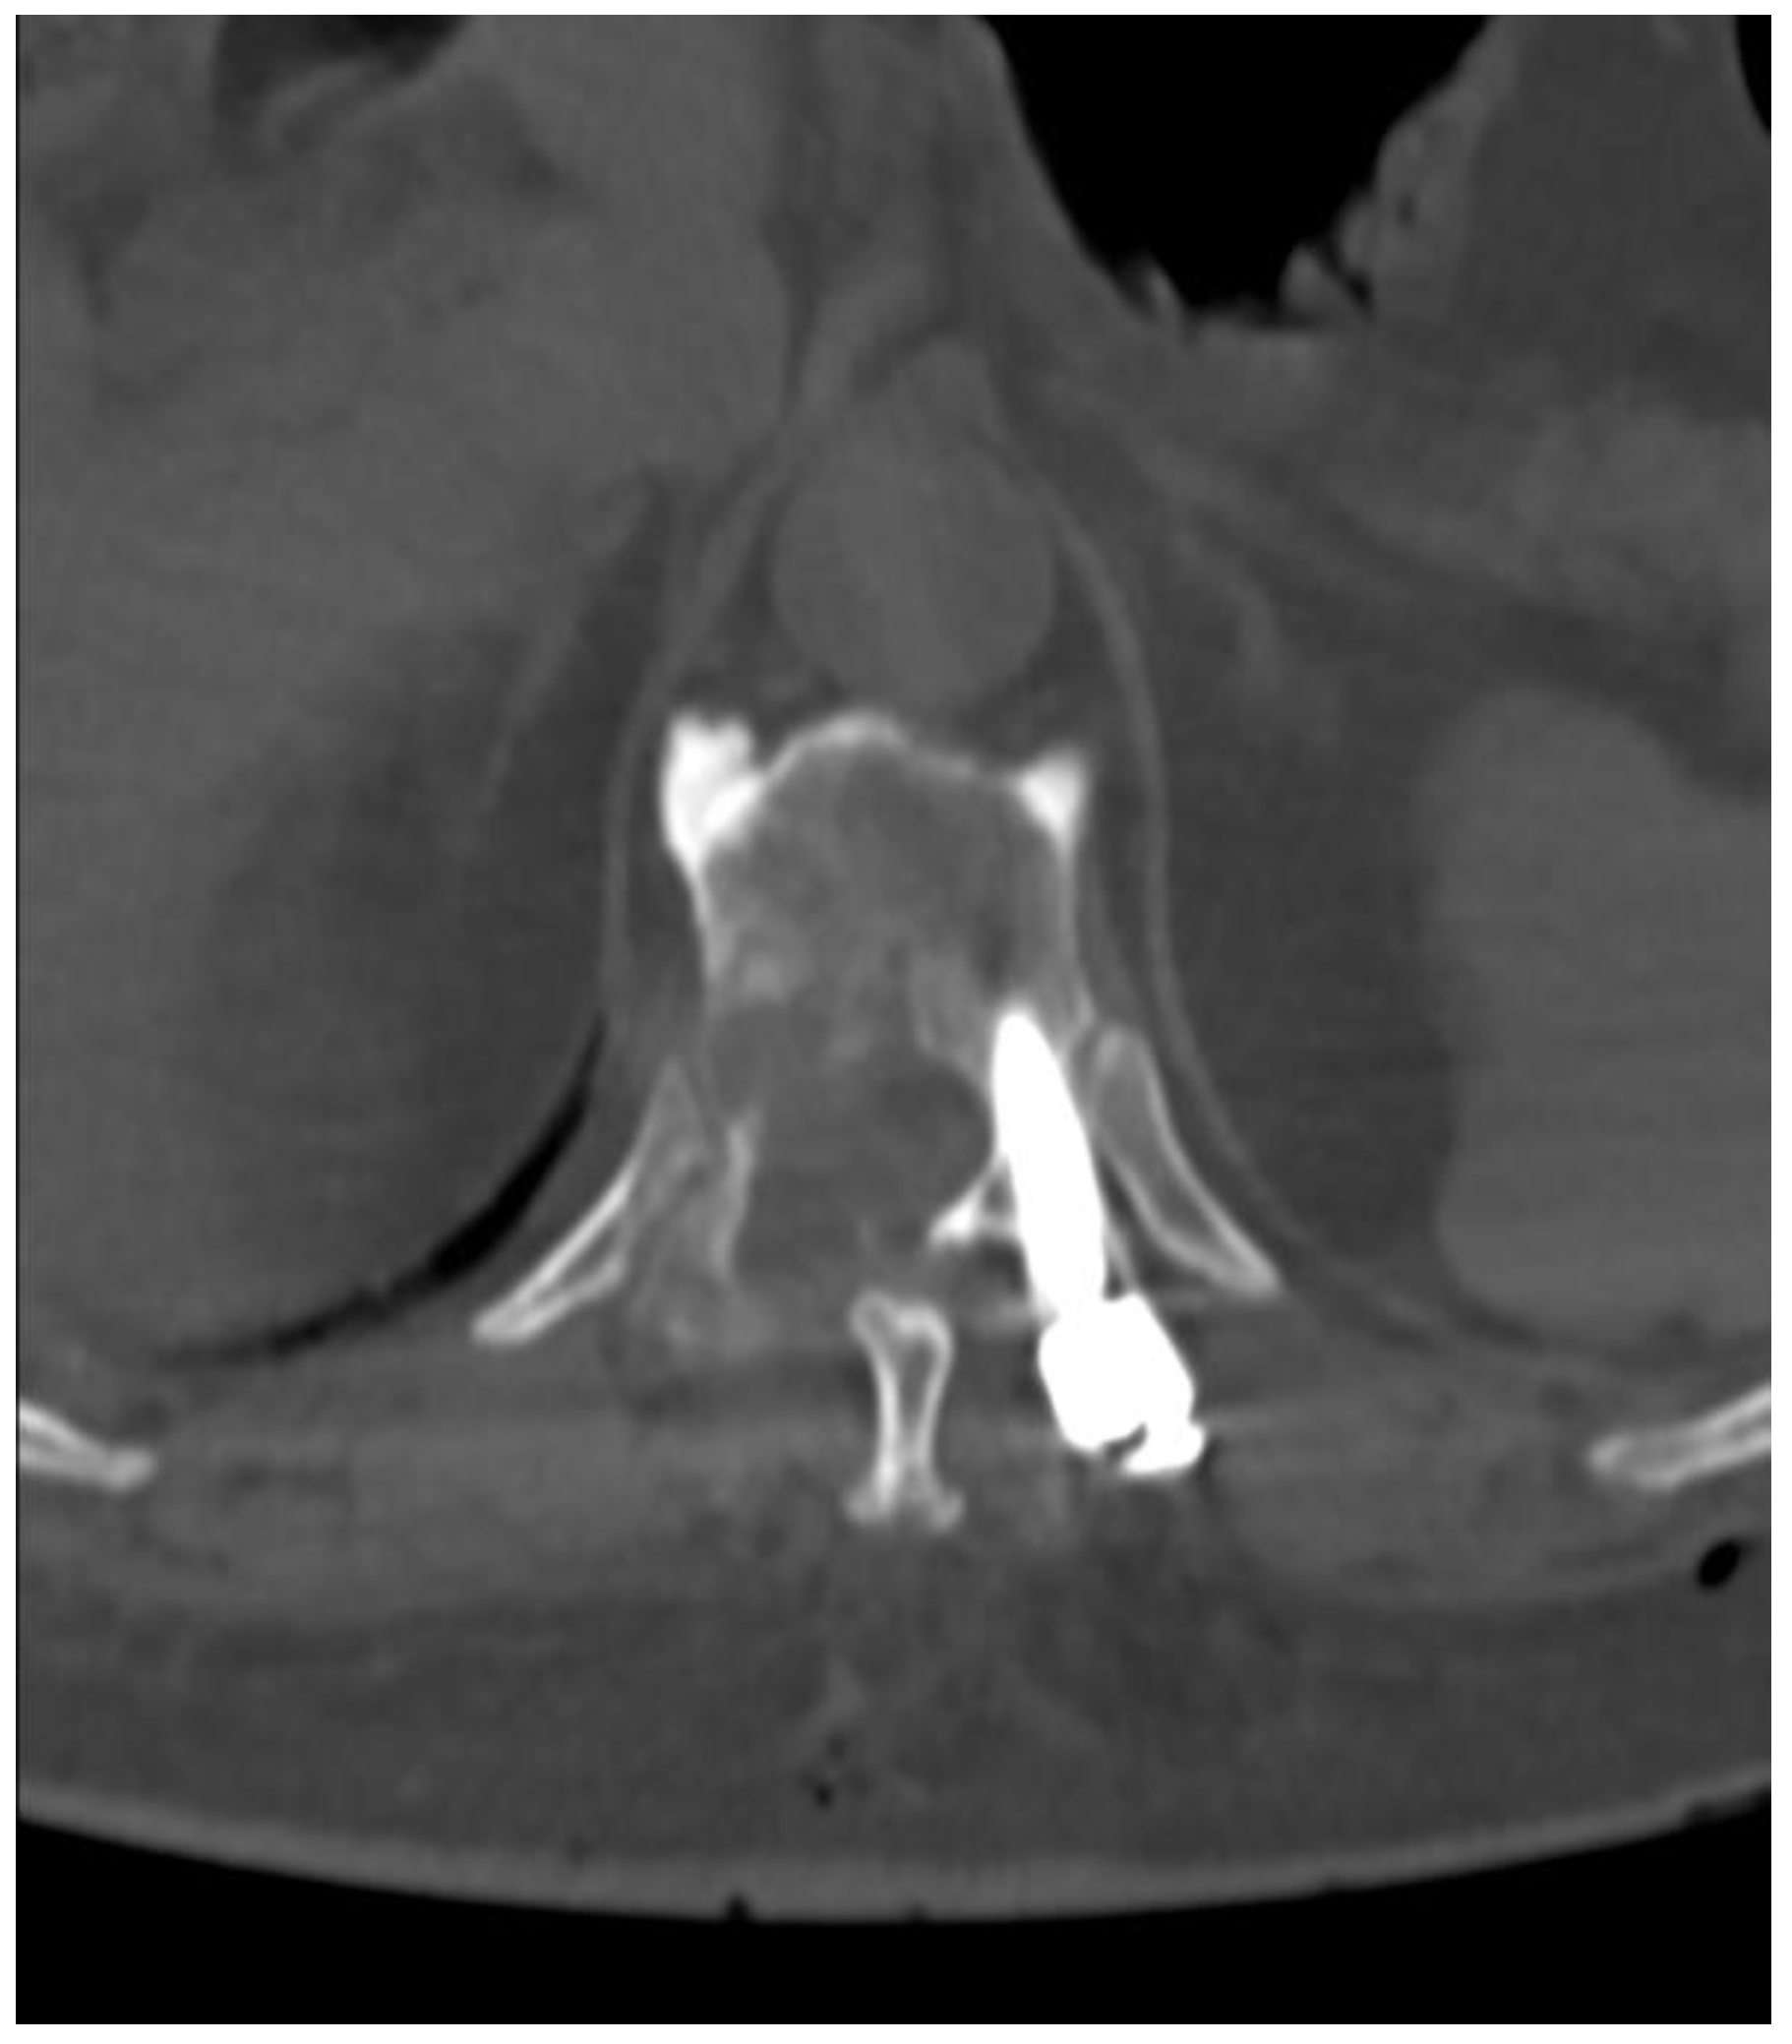

Fully Endoscopic Spine Separation Surgery in Metastatic Disease—Case Series, Technical Notes, and Preliminary Findings

2. Materials and Methods

3. Results